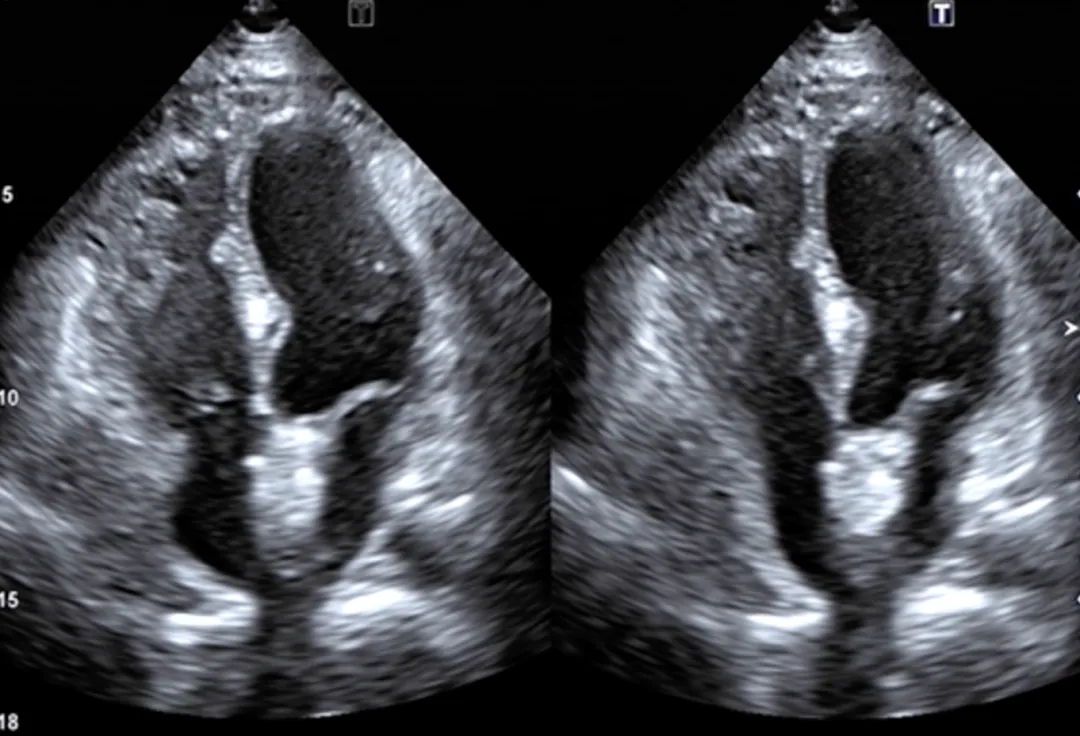

出院前心脏彩超:

PFO封堵术后,未见异常分流,房间隔膨出瘤,二尖瓣少量反流,三尖瓣少量反流,左室室壁运动正常,左室收缩功能正常,左室舒张功能不全I级。

术后3个月复查心脏彩超:

PFO封堵术后,未见异常分流,二尖瓣少量反流,三尖瓣少量反流,左室室壁运动正常,左室收缩功能正常,左室舒张功能不全I级。

三个月随访期间,患者头晕症状显著改善,且未再发生脑梗事件。